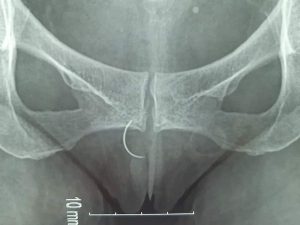

LẤY RA MỘT CÂY KIM NẰM TRONG NGƯỜI HƠN 20 NĂM.

Sáng ngày 29-4 vừa qua, phòng khám phụ sản Bệnh viện Đa khoa Vĩnh Đức [...]